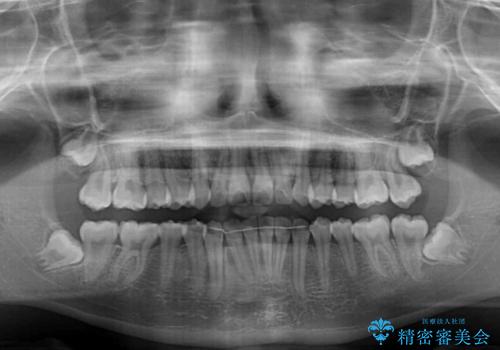

下の前歯が隠れてしまうほど深い咬み合わせ 高校生のインビザライン矯正治療

- 前歯の叢生と深い咬み合わせを気にして来院された患者様です。

奥歯の咬み合わせを見ると、上顎が下顎に対して相対的に前方にありました。

深い咬み合わせを改善するためには、上顎臼歯を後方に移動させつつ、下顎の小臼歯を直立させる必要があります。

インビザライン単体で対応ることも検討できますが、達成する可能性が低いため、カリエールディスタライザーという補助装置を併用して、より確実性を上げることとしました。

奥歯の咬み合わせと深い咬み合わせを改善した後、インビザラインで歯列を整えることとしました。

ワイヤー装置と補助装置を有効に活用し、さらには高校生ということもあり、1年9か月で狙い通りの仕上がりを達成することができました。